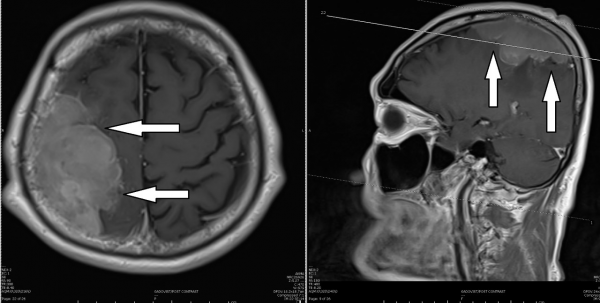

为了进一步诊断,达叔又做了磁力共振扫描,结果在右脑上端顶部发现一颗5x8x4公分的,大小相当于一颗网球,对脑部形成压迫,造成脑水肿和脑压增高,影响了左侧身体的活动,必须开刀切除。

长在右脑上端顶部的脑膜瘤(箭头处),影响了左侧身体的活动。

达叔听后,似懂非懂,一迭声催促我赶快帮他开刀。我先让他服用类固醇,大约一星期后,脑部水肿好转,才替他动手术。一如所料,肿瘤紧贴大动脉生长,为免波及重要血管,我只能切除95%肿瘤,无法完全切除。